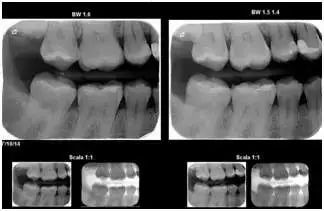

1 咬翼片(也叫龋齿检测X光片)

这种X光片用来观察无法直接看到的牙齿间的部位。

2 根尖片

这种X光片用来观察相邻一颗、两颗或三颗牙齿的整个牙冠和牙根。X光片中也会显示支撑牙齿的骨骼结构。牙医可以通过根尖片,观察乳牙下方的继承恒牙,同时也可以用根尖片找出脓肿,发现牙周疾病。